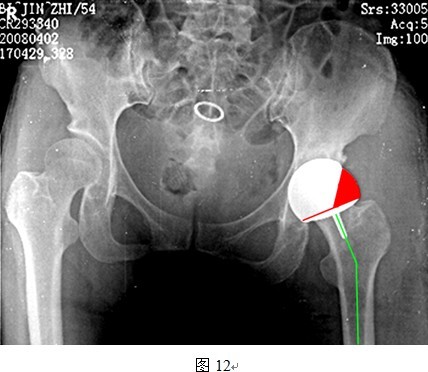

DDH股骨近端的发育异常,颈干角波动幅度较大,在实际应用中,往往无法同时满足上述两个条件。对于合并髋内翻的DDH,即使柄干角较颈干角大5~10度也可能无法达到理想的柄干角(135~140度)。同样,对于颈干角本身就大于140度的患者,若坚持将柄干角再加大10度,则使得柄干角过大,头臼假体包容率减少,造成应力集中,磨损增加(图12所示即为大柄干角与头臼小包容率的关系)。因此,颈干角过大或者过小的DDH患者均不是THRA良好适应症,需要严格筛选。

图中所示,颈干角过大导致柄干角相应增大,间接导致头臼覆盖率下降。